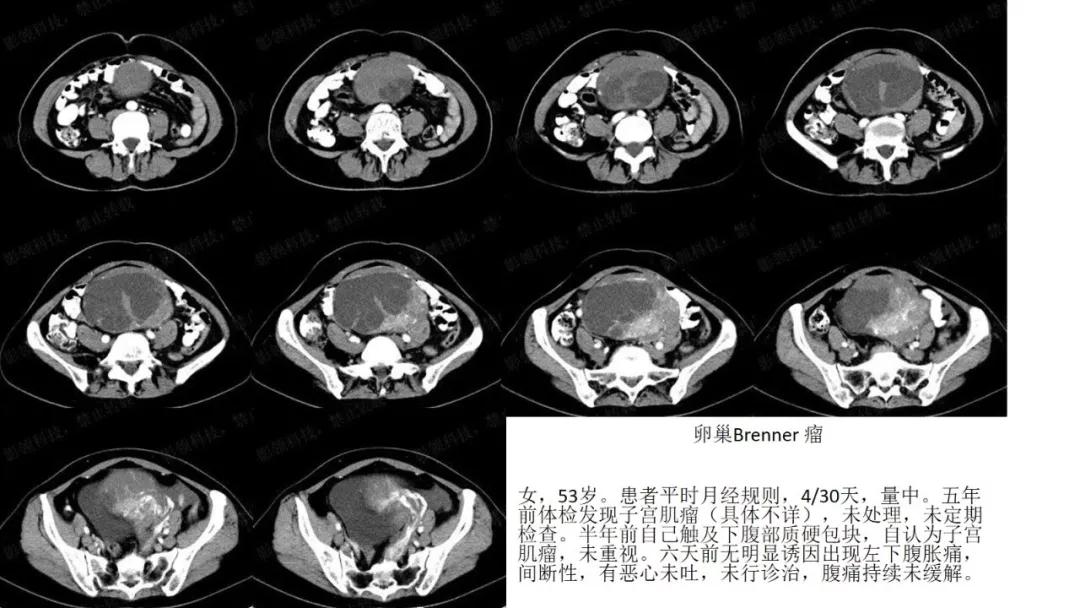

出现钙化:浆液性肿瘤、卵泡膜纤维瘤、畸胎瘤、Brenner瘤

病例10

女,39 岁,体检发现盆腔肿块1月余

CA125:51U/ml

病理:左侧卵巢卵泡膜-纤维瘤